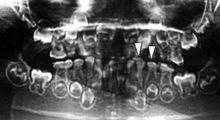

患者牙齒X光片顯示乳光牙隨腔閉鎖趨勢鏡下可見牙本質小管排列紊亂管腔增大單位牙本質中牙本質小管數量減少部分區域牙本質小管消失可見到成牙本質細胞變性合成分泌的基質蛋白異常細胞本身可能被包裹於基質或鈣化的牙本質中牙本質鈣化異常隨著牙齒的進一步磨耗髓腔和根管內不斷形成修復性牙本質最多時可使整個髓腔內被修復性牙本質填滿。

X線片可見早期髓腔較大釉質磨除後髓腔和根管內逐漸出現鈣化閉鎖牙周支持組織正常有時可見殼狀牙(shel tooth)表現為髓腔大牙本質層薄牙根異常短但無根吸收的表現。

患者牙齒X光片顯示乳光牙隨腔閉鎖趨勢